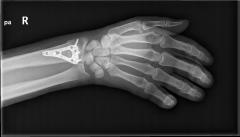

Περίπτωση 1ου ασθενούς